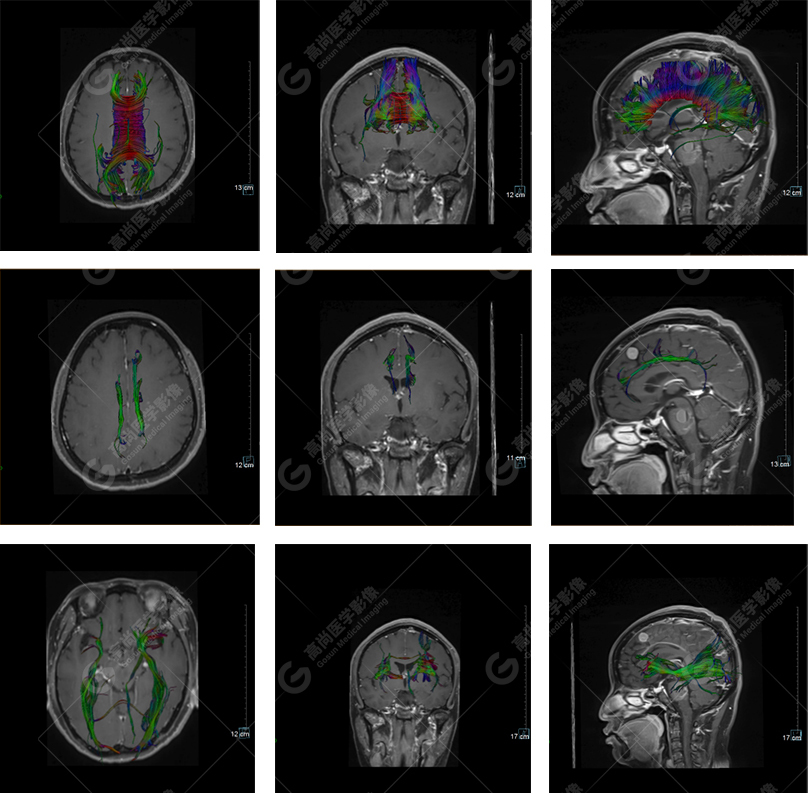

下面是其他神經(jīng)纖維束成像:

胼胝體束、雙側(cè)扣帶束及額枕束形態(tài)可,纖維束未見(jiàn)明顯破壞,未見(jiàn)明顯稀疏減少。大腦鐮旁的病灶對(duì)神經(jīng)纖維束走行并沒(méi)有什么影響。